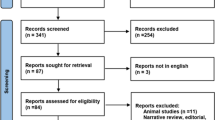

From July 2015 to March 2017, 20 patients with stage I lung tumours or lung metastases referred for stereotactic ablative radiotherapy (SABR) were prospectively included in this study (Table 1). Patients able to understand the instructions related to CPAP and with tumours expected to move significantly (apical tumours excluded) were eligible. One of the patients had two treatments 1 year apart and was recruited twice (#6 and #14). A total of 24 tumours were treated. Histological confirmation was available in 13 patients, who all had primary lung tumours. In other patients, malignancy of the pulmonary nodule was suspected based on imaging features, e.g. morphologic characteristics of malignancy, growth on consecutive CT scans and/or hypermetabolism on positron emission tomography (PET)/CT.

CPAP increased lung volume by 296 mL (SEM: 73; p < 0.001) and 243 mL (SEM: 52; p < 0.001), which corresponds to a mean relative increase of 8.0% (SEM: 2.2) and 6.3% (SEM: 1.3) at T0 and T1 time-points, respectively. The change in lung volume induced by CPAP showed a wide inter-patient variability (Fig. 1 and Table 2). For example, while some of the patients showed a large increase in lung volume at T0 (#16, #18 and #19; Fig. 2), two of the patients (#10 and #13) displayed a slight decrease, for which there is no obvious physiological explanation apart from anxiety (patient #13 was the one who did not tolerate CPAP well). Overall, the change in lung volume induced by CPAP at T0 was similar to T1 (interaction F = 0.31, p = 0.56). However, the intra-patient reproducibility was relatively low (Fig. 1).